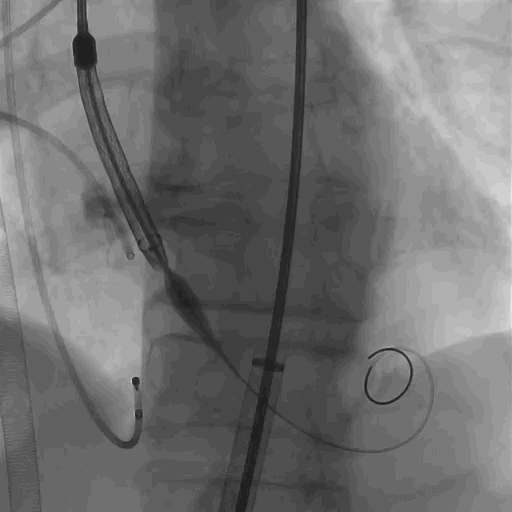

选用启明VenusA L29瓣膜,瓣膜同轴性差,进行调整后选择标准位释放,释放位置良好。

瓣膜释放定位

瓣膜调整后释放

术后造影,反流明显改善,瓣膜工作状态良好。

瓣膜释放完毕

造影观察主动脉弓

患者主动脉根部钙化积分达到1700+,瓣膜置换后即刻跨瓣压差显著下降,反流量明显减少,再行主动脉根部造影后提示瓣膜置入位置良好、形态完整,未见瓣周漏,未出现相关并发症。超声复查下,提示轻度反流存在,手术效果显著。